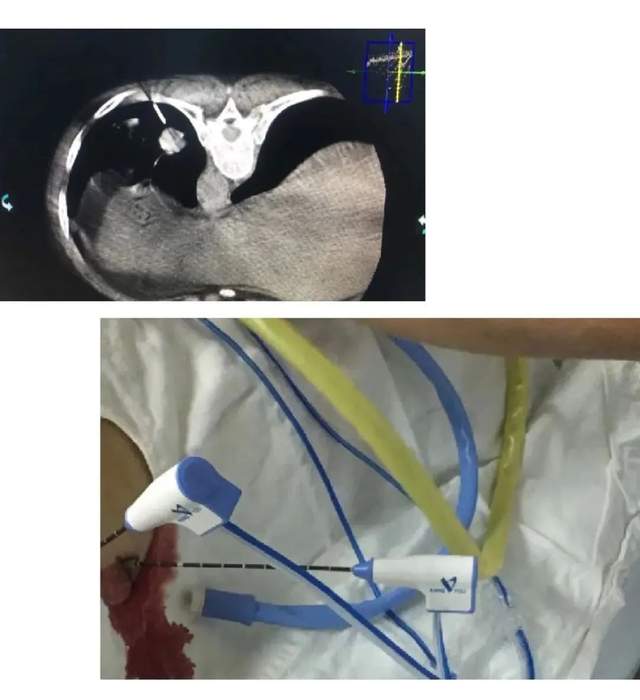

肝肺转移癌射频消融

PTCD(经皮肝内胆管引流)

静脉输液港置入